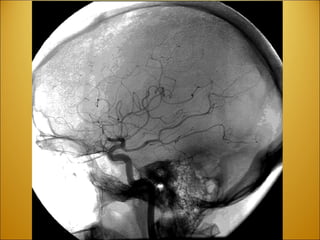

Stroke Ischemic Vs. Hemorrhagic CVA vs TIA Aneurysm Berry @ Basilar/Posterior cerebral  artery SAH